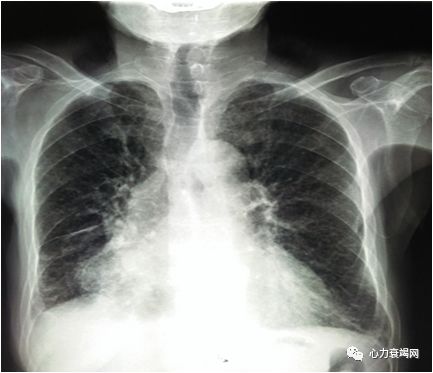

双肺呼吸音粗,双下肺可闻及湿性啰音

心界向左侧扩大,心率76次,律齐,心音低钝,各瓣膜听诊区未闻及病理性杂音

慢性阻塞性肺疾病急性加重期

慢性肺源性心脏病

I型呼吸衰竭

本例患者是一个82岁女性患者,既往明确缺血性心肌病心功能不全病史,反复发生心肌梗死,同时合并COPD,近10余天感染后症状加重入院。入院时端坐位,四肢皮肤湿冷,双下肺可闻及湿性啰音,肝肋下2横指,双下肢重度可凹性水肿,BNP明显升高,心脏超声示全心大,肺动脉高压,左室、右室收缩舒张功能减低,EF 30%,根据其病情为左西孟旦的适应症,使用后患者临床症状缓解,BNP下降。此后患者曾2次因心衰加重入院,均使用左西孟旦治疗,患者入院频率减少,在院时间缩短,肺动脉压明显下降。